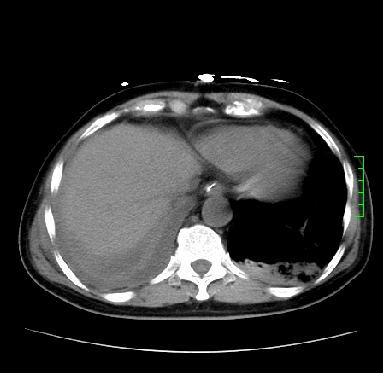

icu病人,几天都没明确诊断。m,76y,咳嗽、咳痰1周,伴气促,右胸痛入院,pe:t38.3c p135 r25 bp135/85。双肺可闻及大量湿罗音,心、腹未见明显异常。诊断:1心衰?2肺部感染?3冠心病?

11号ct